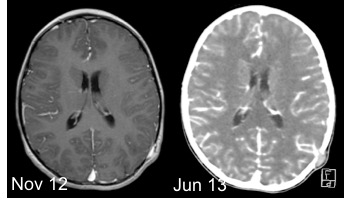

le syndrome de Sturge-Weber-Krabbe

autrefois rattaché aux phacomatoses, il en est actuellement détaché car il n’est ni un syndrome de prédisposition tumorale, ni génétique.

il associe un angiome flamme du visage, généralement unilatéral, un angiome rétinien, et une angiomatose méningée. Cette dernière peut être responsable d’une épilepsie pharmaco-résistante et justifier une chirurgie majeure de déconnexion.